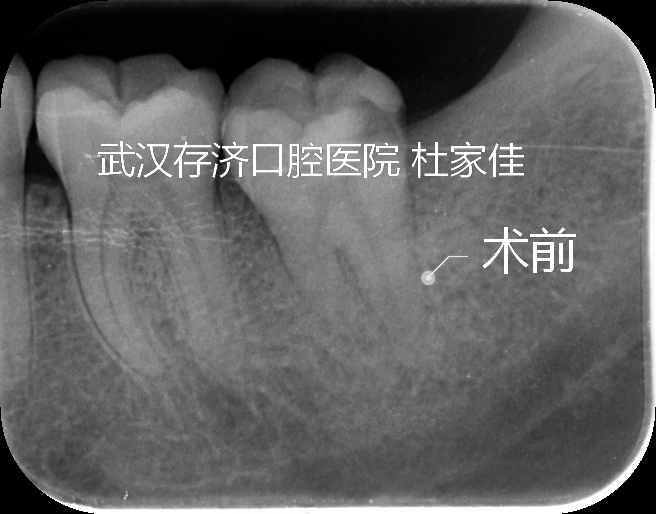

完成根管的机械预备需要具备三方面的知识和能力,一是充分了解复杂根管系统的解剖形态和预备目标;二是充分认识各种金属器械的性能和构造特点;三是熟练掌握各类金属器械的运动模式和操作手法。临床操作中使用的根管器械主要有手动不锈钢锉和机动镍钛锉。根据根管解剖特点和选择合适的器械是应用操作手法及预备技术的基础,完成根管根尖部的感染控制是根管治疗成功的技术关键,而根管系统的解剖结构和器械操作又往往可能成为制约技术实现的因素。

表现为根管的横断面除圆形外,还有卵圆形、扁形、丝带形、"C"形、逗号形、哑铃形、不规则形;根管的纵剖面从根管口到根尖孔总体上由粗到细,至牙本质牙骨质界为最狭窄部位,但在其间任何部位均可存在两根管间复杂的交通网或断续、不规则的连接峡部;在根尖部还可出现特殊的多个分叉的"根尖三角(apical delta)"形态;增龄性变化和牙髓病变造成的根管钙化狭窄、堵塞,内吸收造成的根管局部膨大,根尖外吸收导致的根尖狭窄破坏。

①根尖孔是解剖学概念;②牙本质牙骨质界是组织学概念;③根尖狭窄是解剖学和临床概念。多数根尖孔并不开在根尖顶端,而是位于根尖的一侧。牙本质牙骨质界既为两种硬组织的交界,也是牙髓与牙周这两种软组织的分界,此处通常被认为是根管的最狭窄处,好比山间隘口,一方面有助于机体抵御来自根管的外侵之敌;另一方面,临床上在根管内所施加的任何清创干预性操作也必须止于此,即根管治疗的器械、药品、材料均应限制在该界限以内的空间,禁止跨越到根尖周组织中,否则将造成生活组织的进一步损伤。